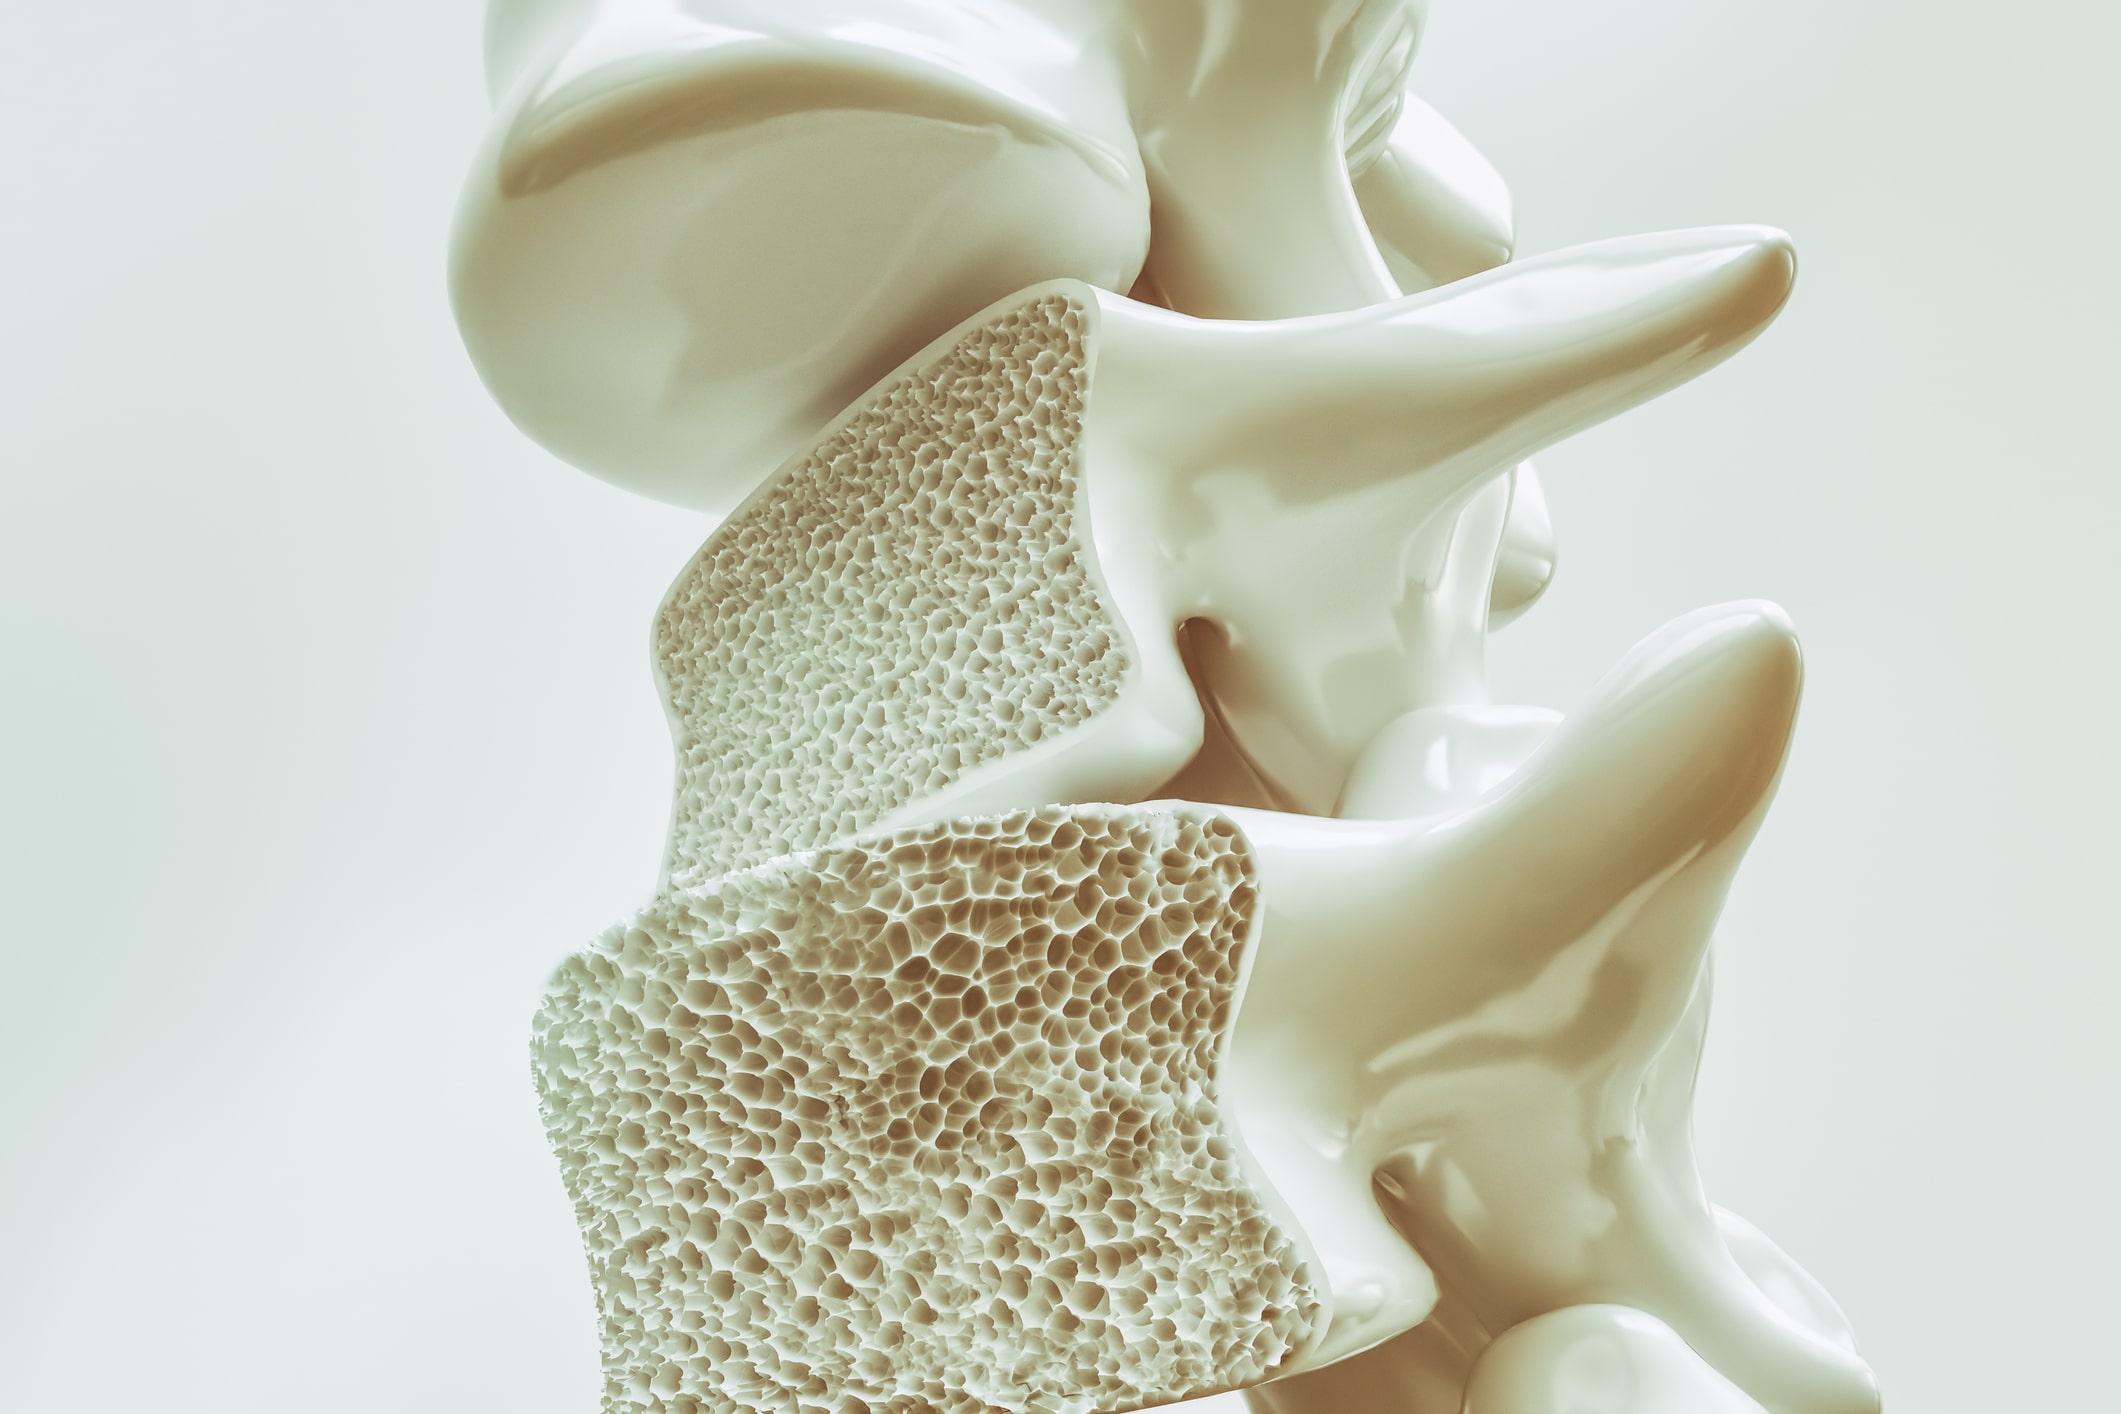

Minerals That Can Help Prevent Osteoporosis

When it comes to osteoporosis, it is often suggested that you get plenty of calcium and vitamin D to keep your bones healthy. But your bones need many more minerals than just vitamin D and calcium. Being aware of these other minerals can help you ensure you incorporate them into your daily diet to keep ...click here to read more